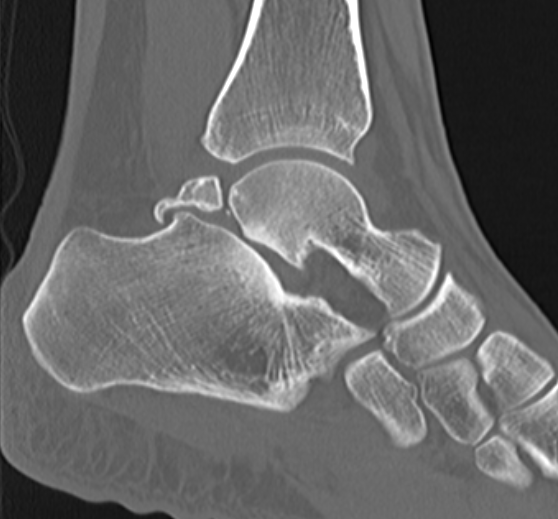

CT

Os trigonum

Fractured Stieda process

Os trigonum with osteochondral fracture posterior tibia